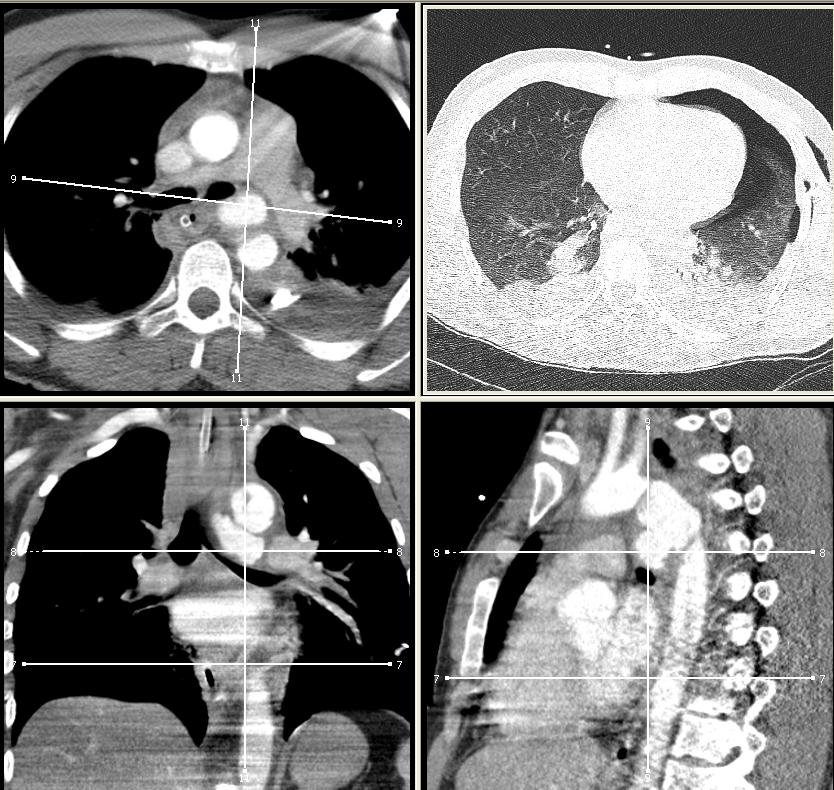

| műtéti leírás alapján: thoracalis stent-grafttal megoldott pulzáló haematoma decelerációs sérülés esetén típusos localisatio az aorta isthmusán |